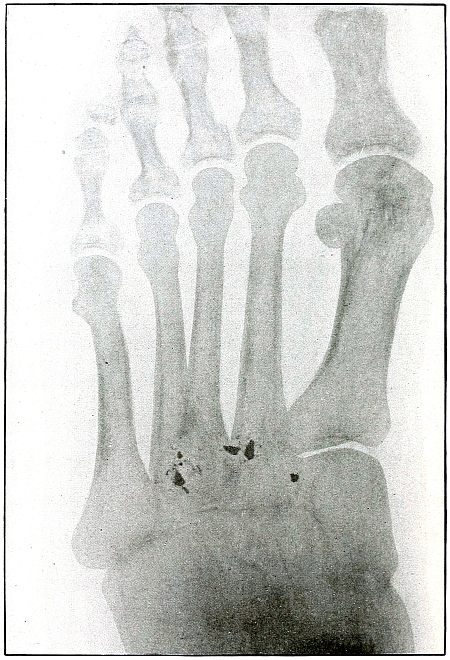

Plate 43.

_

[Pg 97]

Rifle—Plate 43.

UPPER EXTREMITY.

Gunshot Fracture of the Metacarpus.

Wound of entrance, inner aspect of the hand over proximal end of the fifth metacarpal.

Wound of exit, on the outer border of the hand over the distal end of the second metacarpal.

The velocity of the bullet was in mid or long range, as it displaced no fragments, and as it made a point of entrance and exit about the same in appearance.

The wound was infected, which is more frequently the case in the hand than in the forearm.

The treatment is conservative with free incision and drainage in the management of infection. [Pg 98]